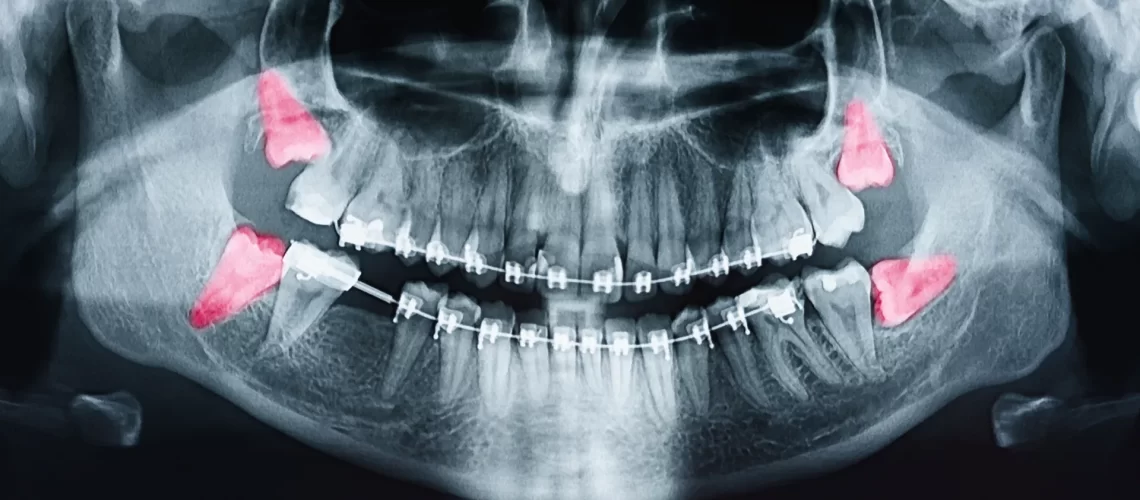

clinical pericornitis

Most adults naturally have 4 wisdom teeth, but about 15-20% of people never develop at least one of these four teeth. What are called wisdom teeth are the third and last molars, which are found at the very bottom on each side of the upper and lower jaws. They are the last teeth to grow through the gums – hence their name wisdom teeth. Wisdom teeth often develop without posing any particular problem. However, sometimes the wisdom tooth does not have enough space to grow and causes severe pain.

There are a number of reasons why wisdom teeth can be painful when they come out. Sometimes it’s a space problem: they put pressure on the other adjacent teeth. It can also be due to the fact that the tooth is stuck sideways or under another tooth. In this case, the gum covering the wisdom tooth can become swollen and infected, which can hurt the jaw or the area around the ear.